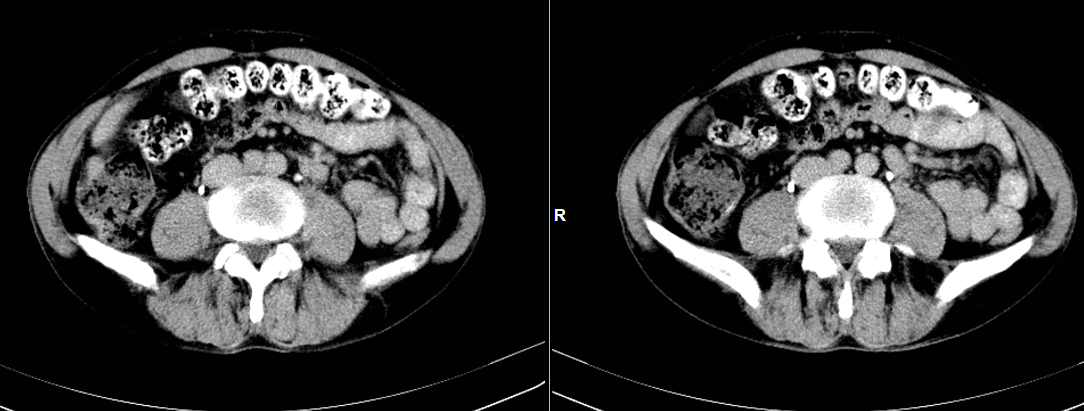

CT49876:肝癌?请各位老师会诊

男性,61岁,体检发现肝占位,自觉腹胀一月余。

原发肝癌伴转移

肝癌伴肝内转移可能性大,不除外转移瘤

考虑肝癌伴肝内转移,不除外均为转移瘤。

原发肝细胞癌,支持

原发肝细胞癌